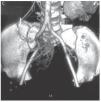

¿ Figura 2. AngioTC, con reconstrucción coronal y proyección de máxima intensidad. Se aprecia una imagen hipodensa, con vasos tortuosos de neoformación con origen en la AMS.